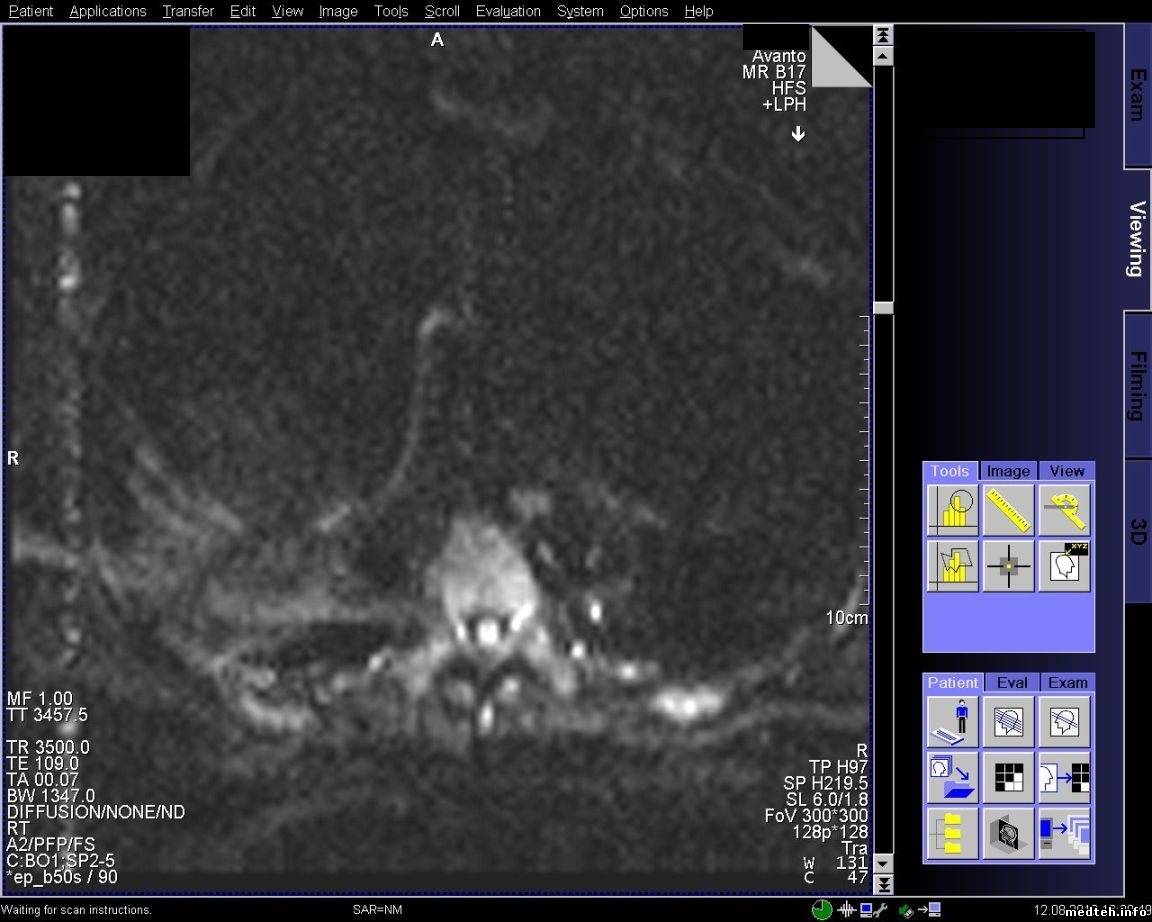

FedorM, спайк чек проходит, адвансед спайк чек не проходит. Выключал свет и инъектор, пробовал в разных комбинациях включать, адвансед спайк чек так и не проходит. Полосы появляются при обследовании с контрастом, но один раз было когда смотрели шею и коленку.

qa_1.pdf (135.4 Kb) · qa_2.pdf (126.1 Kb) · 5814388.jpg (197.7 Kb) · 8772789.jpg (220.4 Kb) · 6614537.jpg (206.3 Kb) · 3268821.jpg (226.4 Kb)

Всем доброго времени суток! Проблема с полосой так и остается актуальной. По снимку и протоколу было выяснено, что частота полосы ориентировочно 20-30 кГЦ, что соответствует частоте работы градиентов. Если гонять rf-noise, то помех (полос) не наблюдается. Полосы появляются на адвансед спайк чеке. Тест гоняли только на боди катушке и при этом если просто фантом лежит, то полоса может быть, а может и не быть. Но на паценте полоса стабильно стоит. Если положить на стол длинный провод и погонять адвансед спайк чек на боди катушке, то полоса стабильно проявляется. Следовательно пациент служит как бы антенной. Частота полосы в 20 кГц наводит на мысли, что неисправность в filter plate. Подскажите пожалуйста, что, где и как ещё можно посмотреть и проверить, если неисправность в filter plate, то как его проверить?